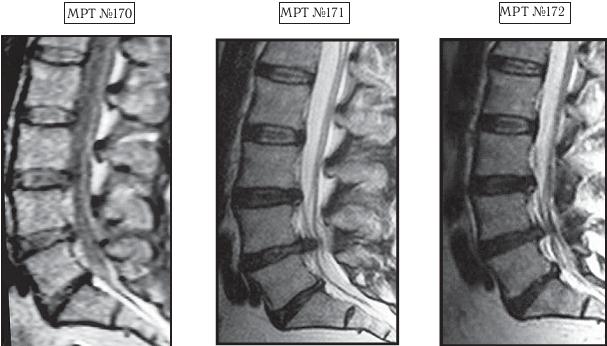

МРТ № 3

На МРТ № 3 — поясничный отдел позвоночника. (На данном «контрольном» снимке наблюдаются остаточные явления дегенеративно-дистрофического процесса в сегменте LV-SI после устранения методом вертеброревитологии секвестрированной грыжи межпозвонкового диска.)

В поясничном отделе форма позвоночного канала, создаваемая телом и дужками позвонка, вариабельна, но чаще она пятиугольная. В норме позвоночный канал в пояснично-крестцовом отделе сужен в переднезаднем диаметре на уровне LIII и LIV позвонков. Его диаметр каудально увеличивается, и поперечное сечение канала приобретает форму, близкую к треугольной, на уровне LV-SI. У женщин канал имеет тенденцию к расширению в нижней части крестцовой области. Сагиттальный диаметр значительно уменьшается от LI к LIII почти неизменен от LIII к LIV и увеличивается от LIV к LV. В норме переднезадний диаметр позвоночного канала в среднем равен 21 мм (15–25 мм).

Существует простая и удобная формула определения ширины позвоночного канала:

нормальный сагиттальный размер не менее 15 мм;

11–15 мм — относительный стеноз;

менее 10 мм — абсолютный стеноз. Уменьшение этого соотношения свидетельствует о сужении канала.

Высота поясничных межпозвонковых дисков 8–12 мм, нарастает от LI до LIV-LV, обычно уменьшается на уровне LV-SI